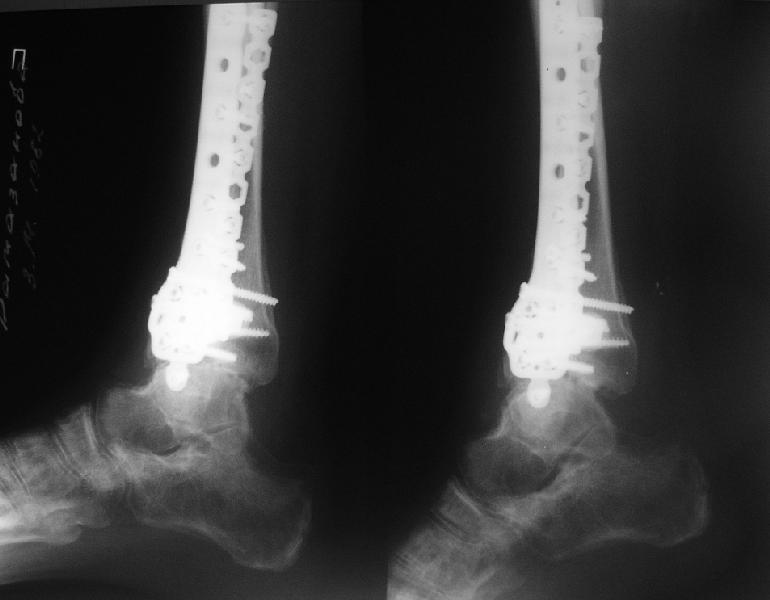

Последствия перелома пилона

Dear коллеги,Обратилась женщина, 25 л. 8 мес. назад в одной из больниц сделан остеосинтез пилона. На сегодня ходит без дополнительной опоры, хромая на поврежденную ногу. Движения в голеностопном суставе еще есть. Снимки в приложении.

Вопрос - что делать? Замыкать сустав пациентка пока не настроена (наверно, получится настроить, если задаться такой целью). Нет ли смысла попытаться сделать какую-то восстановительную операцию?Допустим, получится устранить подвывих, восстановить межберцовые соотношения - это что-то хорошее надолго даст? Или упросто убрать "железо", и этим ограничиться, пока сама не придет за артродезом?

Есть ли здесь смысл пытаться организовать эндопротезирование? В смысле, доступные сейчас протезы применимы в этой ситуации?

A female, 25, 8 month ago operated elsewhere. To date walks without support with pain and limp. The ankle is mobile yet. Images attached.The question is what to do now? The patient is not very keen on ankle fusion (though likely could change her mind if necessary)Is it worth to try a reconstruction procedure and what kind? Maybe it allows to restore alignment and tibio-fibular relationship - will it provide painless limb for more or less significant time?Or just remove the hardware and leave her alone until she herself comes for fusion?

Are available total ankle implants suitable for the situation? If yes what one?

She has an intraarticular screw on CT, best is to remove all and wait untill she asks for fusion.

CT images/xrays confirm incongruity of articular surfaces as well as intraarticular screws.

removing just those screws which have penetrated the joint may take some pain away.

Александр, добрый вечер! К сожалению, боюсь, что, кроме артродеза, ничего не осталось, упущено время. Просто убрать железо конечно можно, а куда деть вальгусную установку, "синдесмоз", признаки артрофиброза, которые прослеживаются на представленных рентгенограммах. Вопрос же стоит в качестве жизни пациентки, может ей тактично все объяснить, что чем дольше она будет так ходить, тем возможно болевой синдром будет более стойким и усилится деформация.